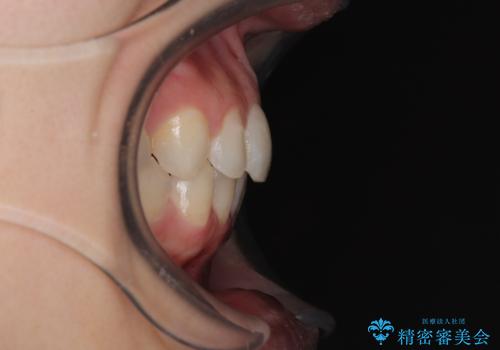

- 前歯のデコボコと歯肉に埋もれている奥歯を気にして来院された患者様です。

インビザラインでの治療を希望されていましたが、左右の下顎大臼歯が歯肉に埋もれており、特に右側は歯軸が顕著に傾斜していたため、インビザライン単独での治療は困難と判断し、ワイヤー装置を併用することとしました。

ワイヤー装置での下顎臼歯改善には時間がかかることが予想されたため、下顎のワイヤー矯正と並行して上顎をインビザラインで整え、その後インビザラインにより上下歯列を整える矯正治療を行うこととしました。

ワイヤー装置を併用したことで、レントゲン写真からも分かるとおり歯軸をしっかりと改善させることができました。